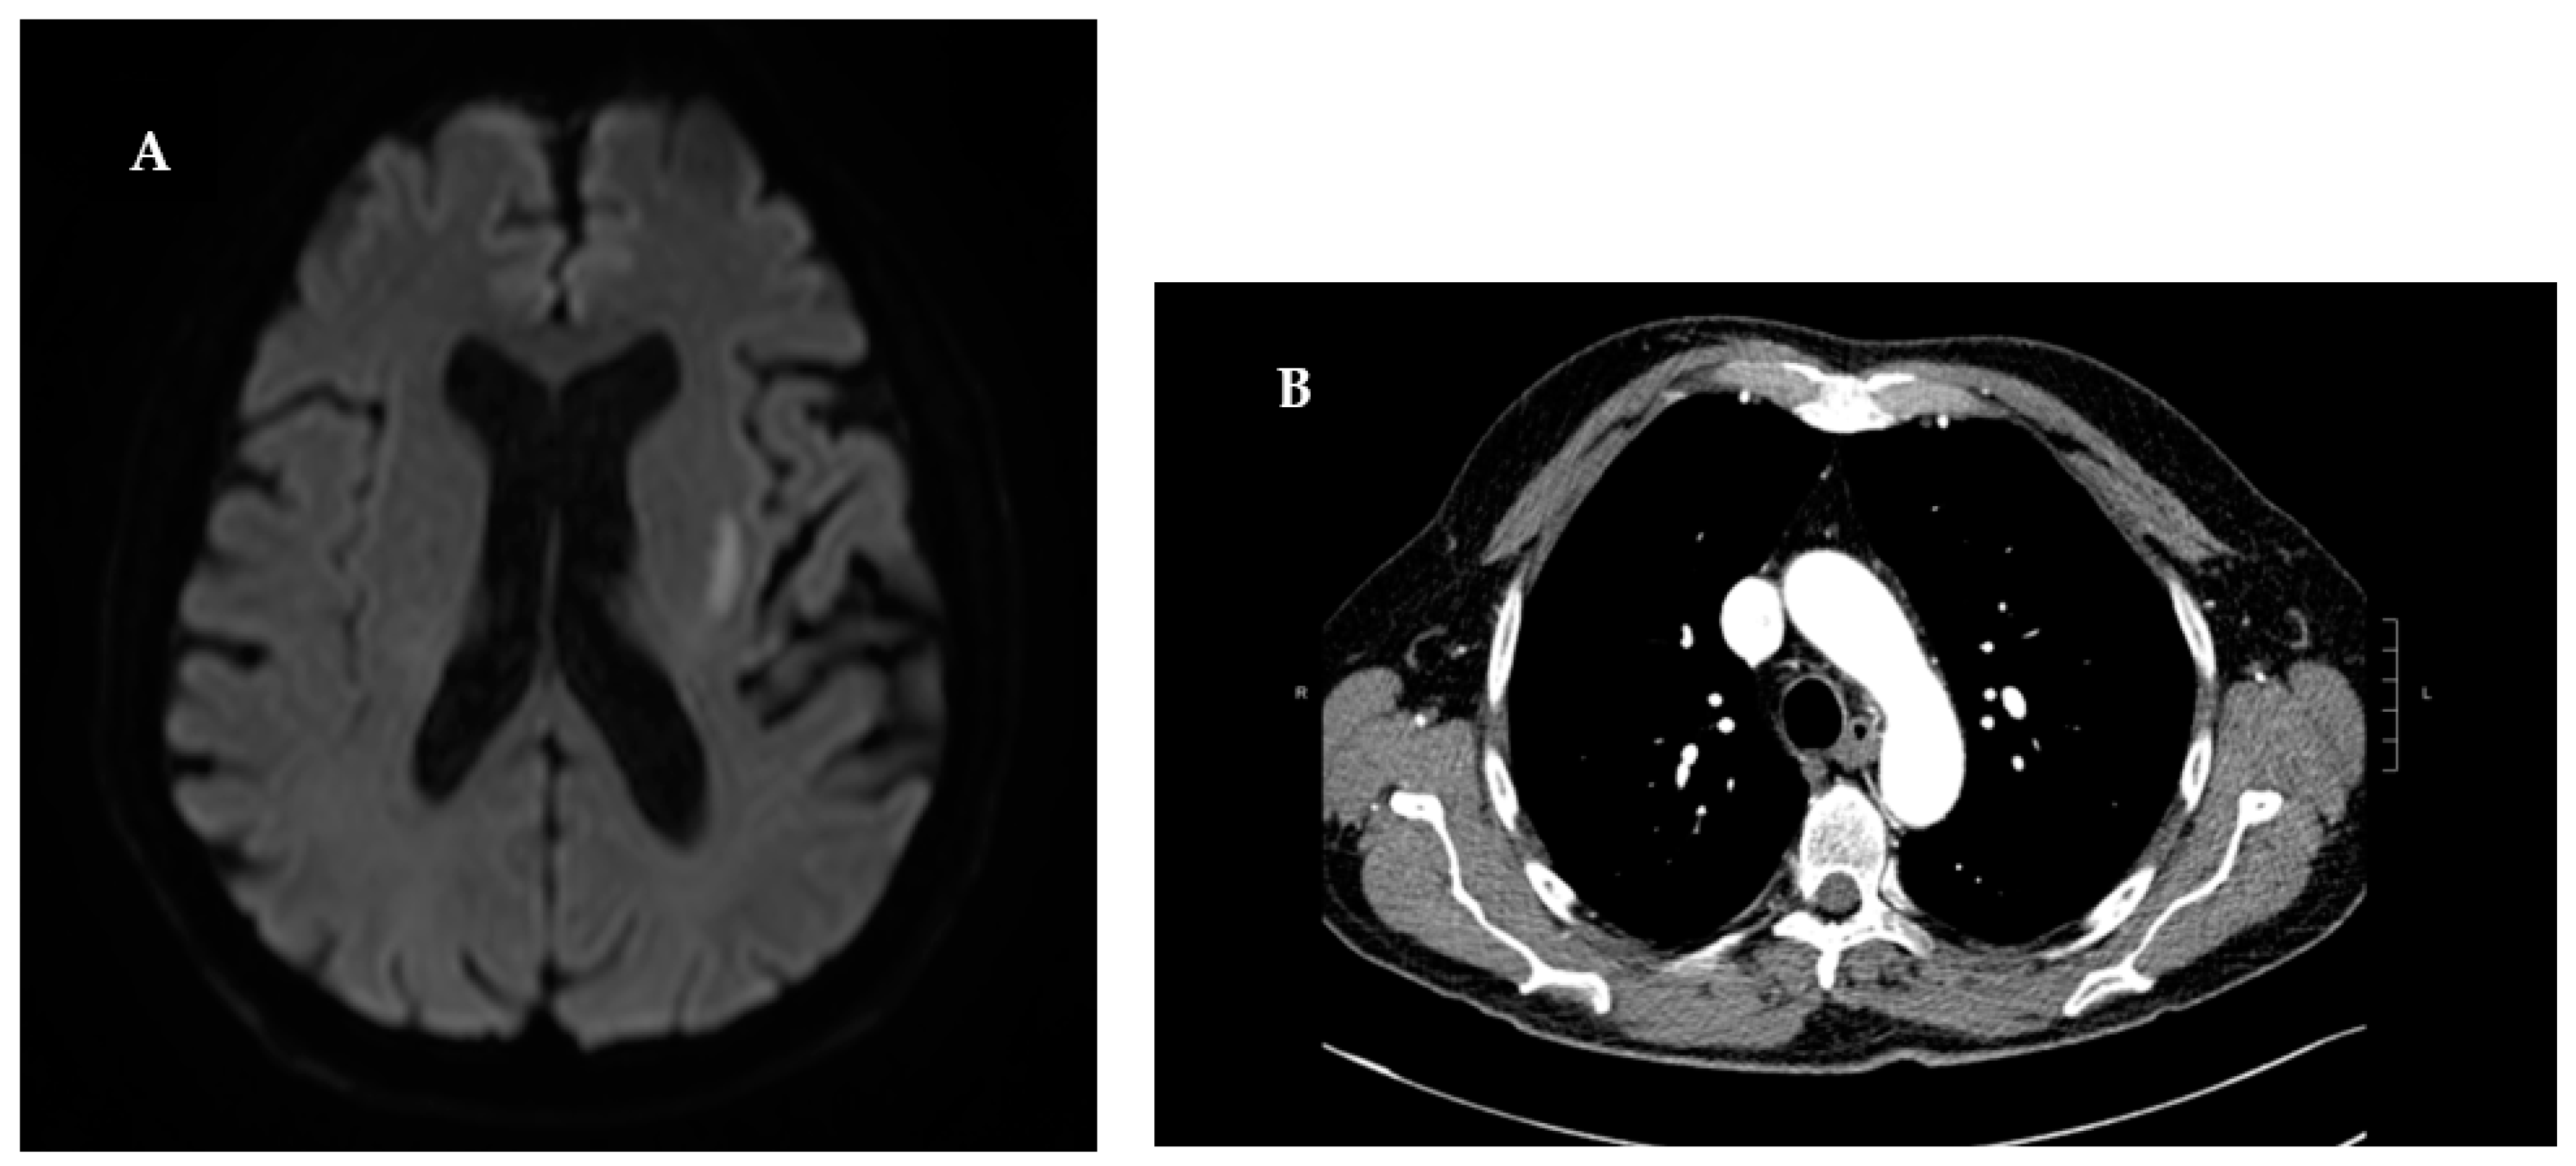

With an initial clinical suspicion of ischemic stroke, the patient underwent an immediate cranial computer tomography (CT) scan. The scan showed evidence consistent with severe chronic microvascular leukoencephalopathy. To definitively exclude an acute ischemic event, the patient was subject to brain Magnetic Resonance Imaging (MRI). The diffusion- weighted imaging (DWI) at high b values (b=1000s/mm^2) indicated an area of restricted proton diffusivity within the left striatum, consistent with an acute ischemic stroke (Figure 1). Since there was no visible large vessel thrombotic occlusion, it was not possible to perform cerebral angiography with mechanical thrombectomy. Moreover, due to more than 4 and a half hours having elapsed since the onset of symptoms, the patient did not meet the eligibility criteria for intravenous thrombolysis [12]. In accordance with the American Heart Association/American Stroke Association guidelines for the Early Management of Patients With Acute Ischemic Stroke [13], the patient received a 40mg Omeprazole injection in 100 cc of saline solution during the acute phase, followed by a 300mg loading dose of Salicylic Acid. For secondary prevention, the patient’s treatment regimen was supplemented with Aspirin 100 mg and Atorvastatin 40 mg. The laboratory test values showed an increase in inflammation indices and renal function (Table 3).

This discovery prompted consultation with Rheumatology department, who recommended a chest CT scan to rule out pulmonary involvement, and nephrological assessment to explore potential renal implications. The chest CT scans disclosed parenchymal consolidations of pseudo nodular morphology with finely irregular borders, findings consistent with initial lesion of GPA.A week post the admission, renal function was repeated with results indicating creatinine levels at 1.2 mg/dl, blood urea at 90 mg/dl, and a creatinine clearance of 26.5 ml/min. Further nephrological evaluation unveiled a 24-hour proteinuria of 640 mg/dl. Subsequent urinary sediment analysis exhibited the presence of red blood cells (228/µL) and numerous acanthocytes. To identify any additional renal abnormalities, an ultrasound of the urinary tract was performed. However, this only revealed the presence of renal calculi. The investigations conducted were consistent with GPA, satisfying three out of four diagnostic criteria of ACR/EULAR 2022 with a score exceeding 5 points.[14]Lastly, considering the potential PNS involvement in cases of GPA and the physical examination indicating the involvement of the CPN, the patient underwent a nerve conduction study and electromyography (ENG/EMG). Neurophysiological assessment revealed a multi-neuropathic pattern of peripheral nerve trunk impairment, with pronounced involvement of right CPN.

Figure 1. A) The diffusion- weighted imaging (DWI) at high b values (b=1000s/mm^2) indicated an area of restricted proton diffusivity within the left striatum, consistent with an acute ischemic stroke B) Parenchymal consolidations of pseudo nodular morphology with finely irregular borders.